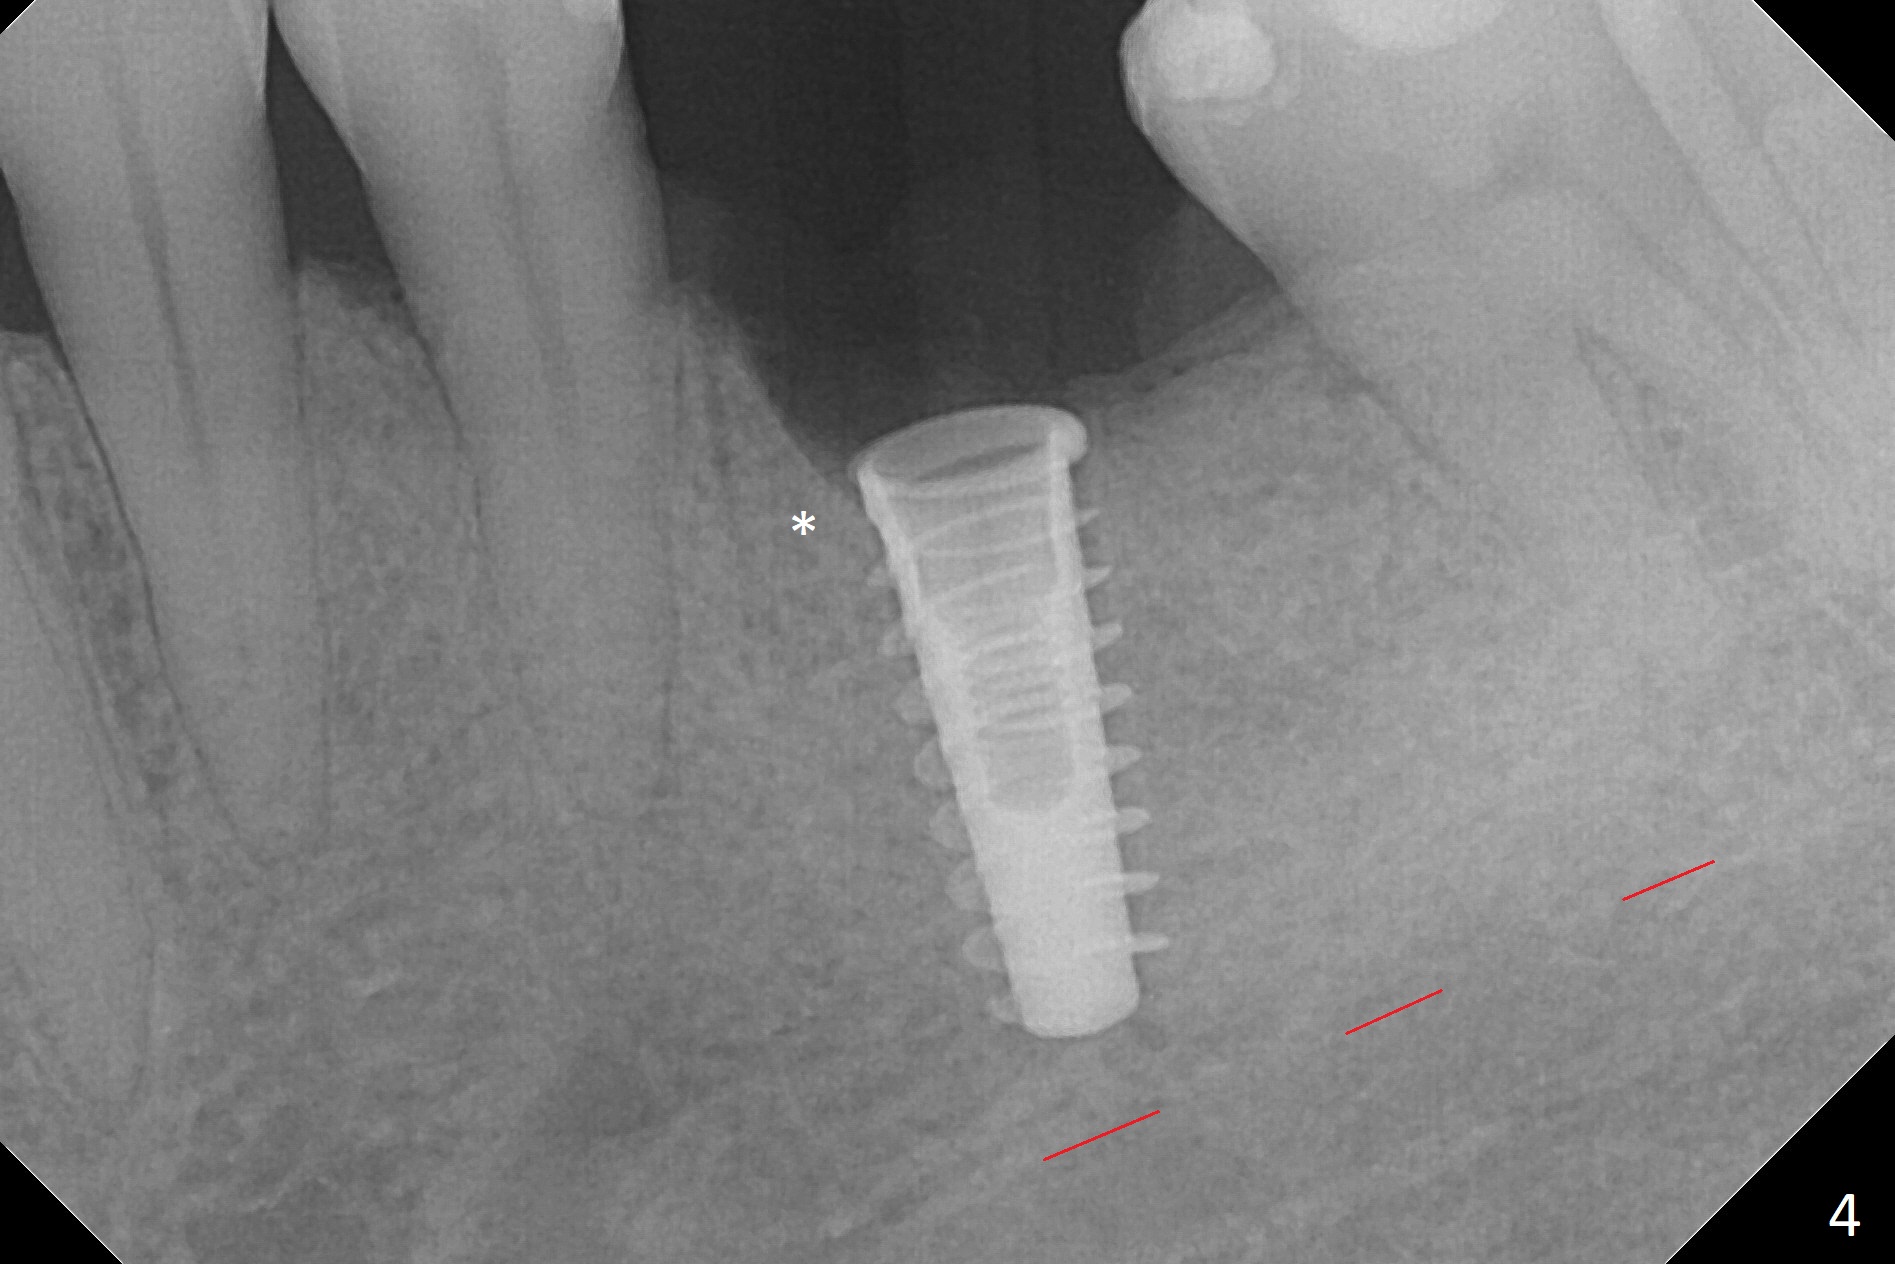

While the mesial ridge is relatively wide associated with residual root at #19 (Fig.1 <), the distal one is narrow (*). Osteotomy is initiated distal to the mesial socket (Fig.2,3 *). Due to the narrow ridge, a 4.5x11 mm implant is placed (Fig.4); before as well as after placement of a 6x4(3) mm abutment, the mesial socket (*) is filled with Vera graft and autogenous bone as well as collagen plug. Following suturing, periodontal dressing is applied to the wound. There is no apparent bone loss 7 months postop (Fig.5,6) or 14 months post cementation (Fig.7). In fact the abutment has been incompletely seated (Fig.5-8), which may be related to #13 failure. The ridge appears to be narrow for the 4.5 mm implant 1.5 years post cementation (Fig.9). When a lady looks skinny with sign of the narrow ridge, choose an implant as narrow as possible.